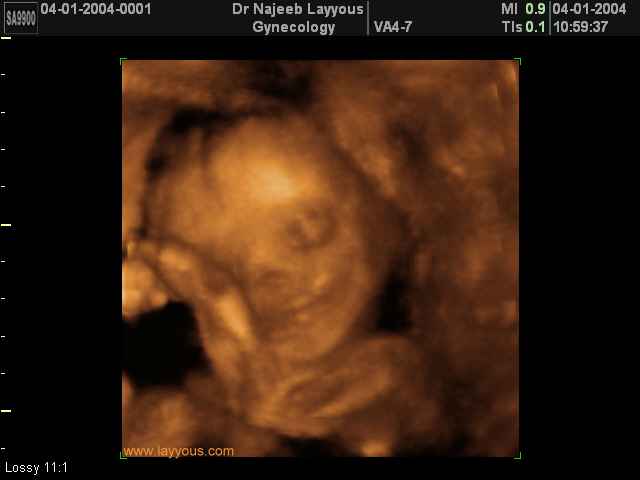

- Fetal Behavior Ultrasound Photos

Ultrasound Photos in 3D showing Fetal Behavior Inside the uterus | Dr N Layyous